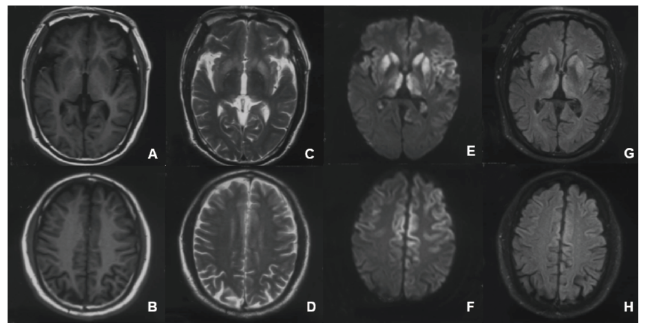

血常规、血生化、血脂、血清铜、铜蓝蛋白、甲功、叶酸、维生素B12、同型半胱氨酸、心肌酶谱、ASO、RF、抗核抗体谱定量、病毒全项、梅毒抗体、莱姆病DNA、AFP、CEA、CA19-9、PSA、尿常规、大便常规未见明显异常。肝功:总蛋白 64.5 g/L,总胆红素 34.98 μmol/L,直接胆红素 6.12 μmol/L,间接胆红素 28.86 μmol/L,尿酸 538 μmo1/L。血浆乳酸测定:2.40 mmo1/L。TORCH:风疹病毒IgG抗体(+)、巨细胞病毒IgG抗体(+)、单纯疱疹病毒IgG抗体(+)、细小病毒B19 IgG抗体(+)。完善脑脊液检查:压力为105 mmH2O,有核细胞1×106/L,蛋白0.36 g/L,葡萄糖 2.99 mmol/L,氯 127.2 mmol/L,脱落细胞可见少量成熟淋巴细胞;单纯疱疹病毒、EB病毒、巨细胞病毒DNA未见异常。自身免疫性脑炎抗体谱(江苏先声医学诊断),包括 NMDAR、LGI1、CASPR2、GABABR、AMPAR1、AMPAR2示阴性。脑脊液14-3-3蛋白(中国疾病预防控制中心)示阳性。血PRNP基因序列(中国疾病预防控制中心)未发现突变,129位氨基酸多态性为M/V型,219位氨基酸多态性为E/E型。神经心理学检查:小学学历,MMSE 24分,MoCA 17分,NPI 4分。视频脑电图示发作间期脑电图,未见明显异常。颅脑MR平扫和增强:双侧基底节、丘脑、额顶叶皮层多发对称性异常信号,代谢性脑病或克雅氏病待排,请结合临床进一步检查。(见图1)

图1 患者颅脑MRI平扫

A、B)T1轴位,C、D)T2轴位,E、F)DWI轴位,G、H)FLAIR 轴位,示双侧基底节、丘脑、额顶叶皮层多发对称性异常信号。

Fig.1 Patient Brain MRI scan

A、B) T1WI axis,C、D)T2WI axis,E、F)DWI axis,G、H)FLAIR axis,Multiple asymmetric signals in bilateral basal ganglia, thalamus and frontal parietal cortex